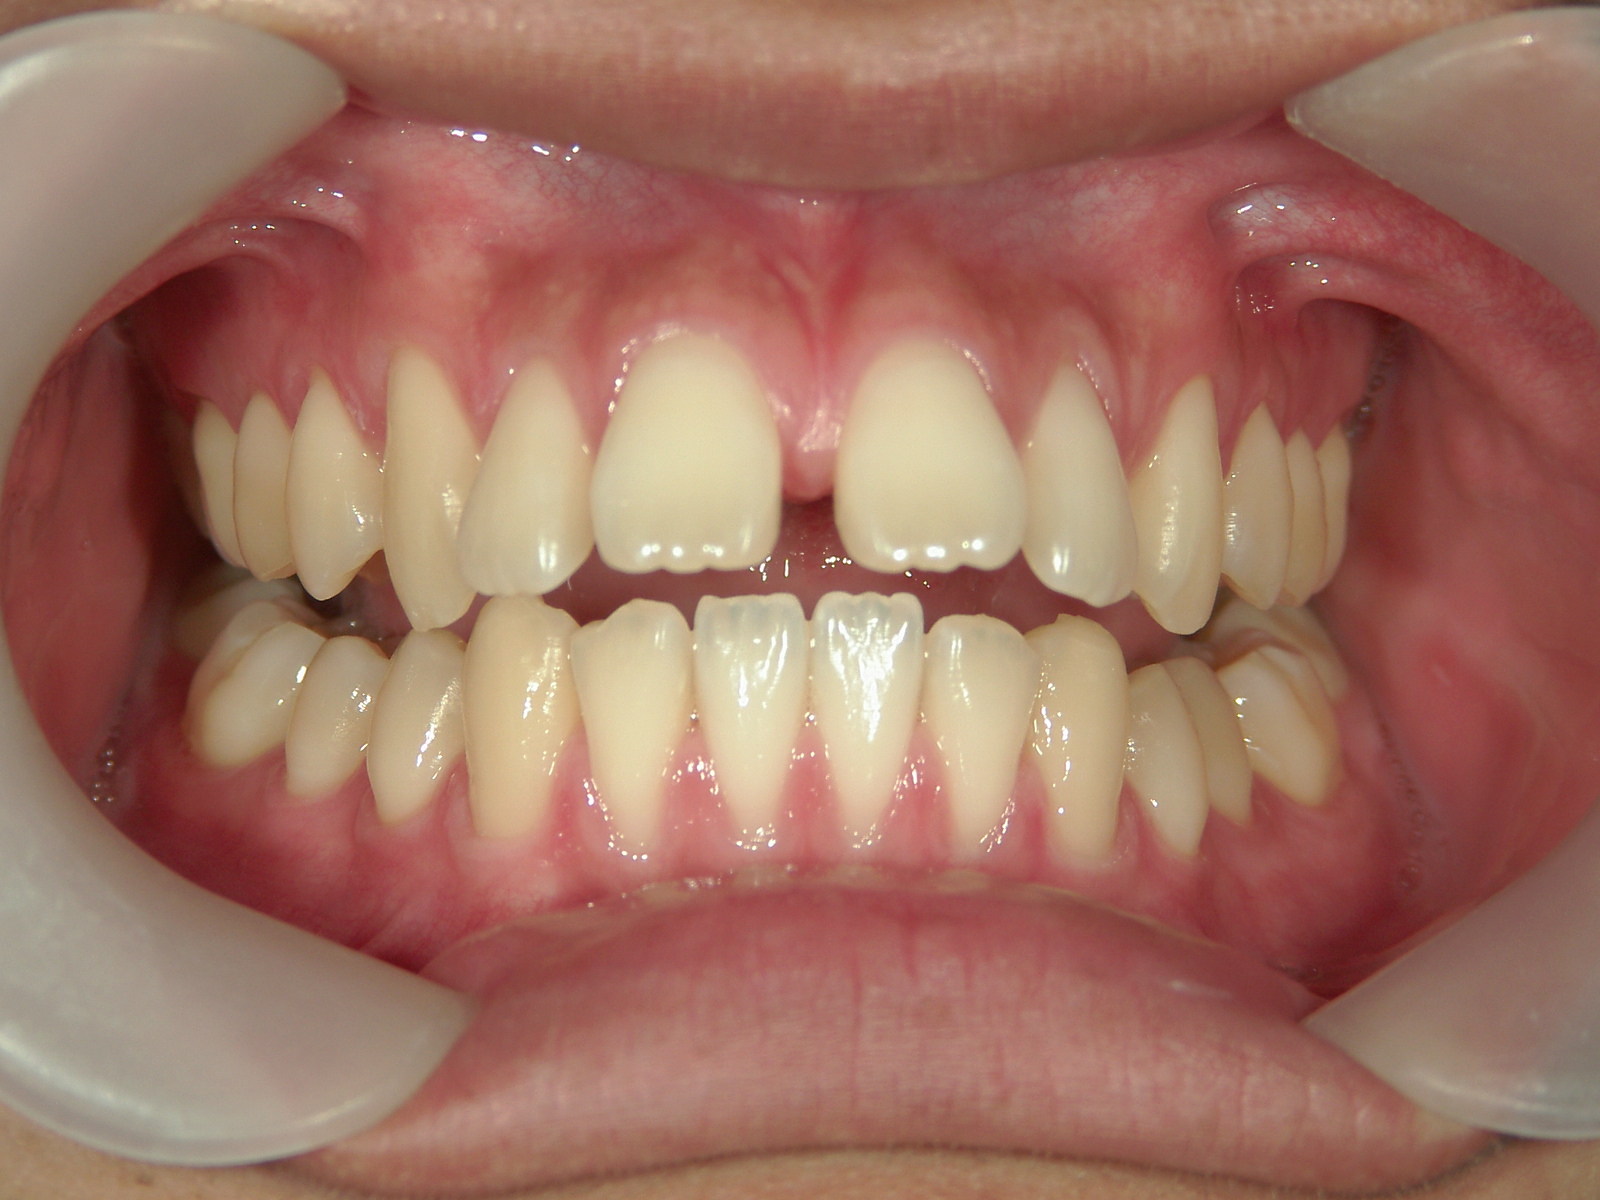

インビザライン矯正 症例(24)

主訴: 前歯の隙間が気になる。

カテゴリー : 隙間がある(空隙歯列)